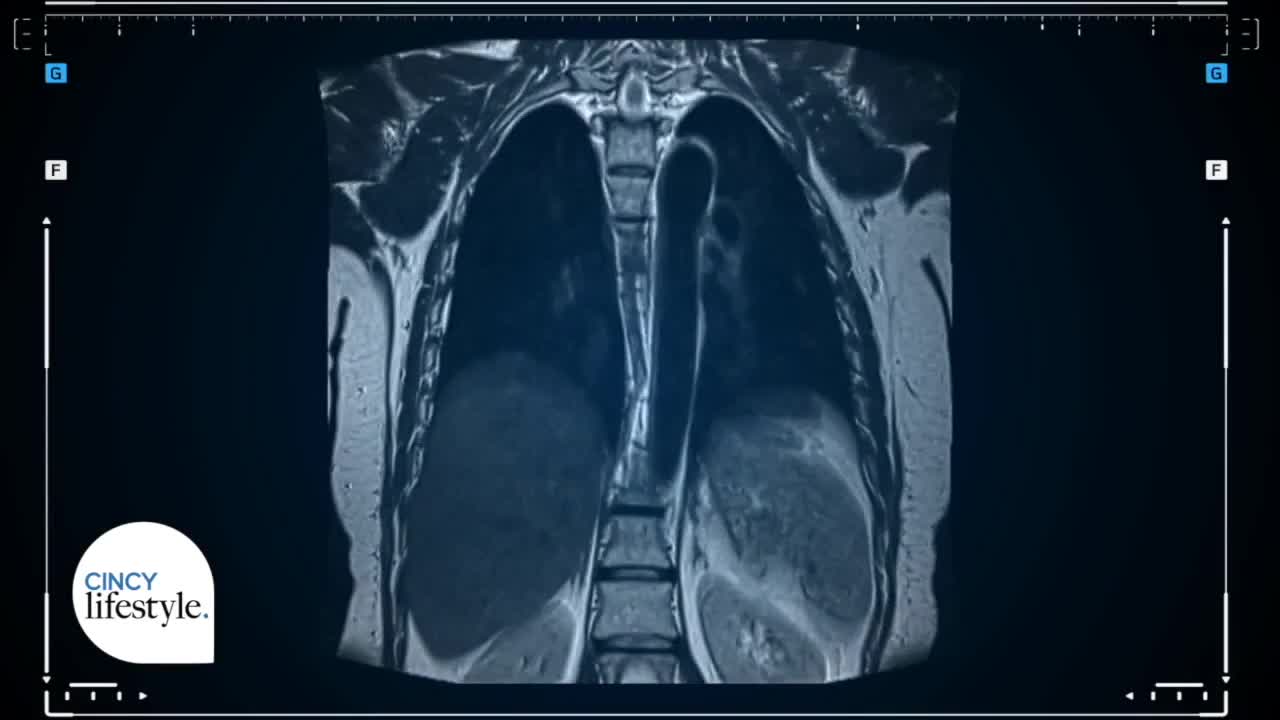

Lung and esophageal cancer can be hard to detect early, often showing no clear symptoms. Dr. Costanzo DiPerna from Mercy Health explains how their experienced team uses screenings, surgery and modern therapies to help patients. With a coordinated approach involving pulmonary experts, oncologists and radiation specialists, Mercy Health aims to find cancer sooner and offer the most effective treatments. For more information, visit www.mercy.com